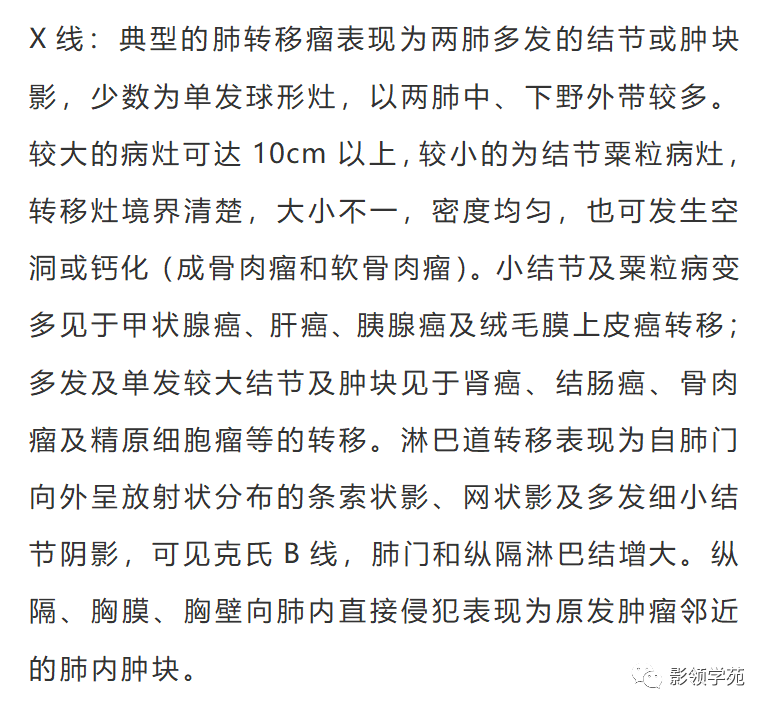

转移途径有血行转移、淋巴道转移、直接侵犯、以血行转移最多见。那么,肺转移瘤的影像都有什么特点呢?今天小编来说一说!

血行转移:瘤栓到达肺小动脉及毛细血管后,可浸润并穿过血管壁,在周围间质及肺泡内生长,形成肺转移瘤。

淋巴道转移:肿瘤细胞穿过血管壁侵入周围淋巴管,形成多发的小结节病灶。常发生于支气管血管周围间质、小叶间隔及胸膜下间质,并通过淋巴管在肺内播散。

肿瘤向肺内直接转移的原发病变为胸膜、胸壁及纵隔的恶性肿瘤。